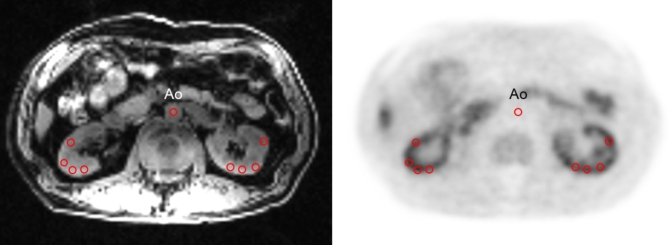

本研究采用正电子发射断层扫描联合磁共振成像(PET/MRI)技术,采用64cu -二乙酰基-双(n4 -甲基硫代氨基甲酸酯)(64Cu-ATSM)作为OS显像的PET示踪剂,探讨慢性肾病(CKD)患者肾脏氧化应激(OS)及其与疾病严重程度的关系。30例CKD患者(66.4±8.2 y.o)和7例健康对照(HC)患者(58.3±3.8 y.o)行64Cu-ATSM PET/MRI检查。参与者根据肾小球滤过率(eGFR)分为三组:HC、轻度CKD (2-3a期)和晚期CKD (3b-5期)。所有受试者从注射64Cu-ATSM开始,接受30分钟动态PET/MRI检查,评估肾血流量(RBF)和OS水平。根据前3分钟PET数据计算RBF (mL/min/100 g)图像,并从注射后15-30分钟的延迟帧获得标准化摄取值(SUV)图像。使用单个RBF图像将64Cu-ATSM SUV图像校正为RBF调整后的SUV,使用以下公式估计单个肾脏的OS水平:调整后的OS指数(aOSi) = (SUV/RBF)x100。eGFR与RBF有显著相关性(r = 0.81),三组间p64cu - atsm SUV无显著性差异(P = 0.171)。在HC受试者或CKD患者中,64Cu-ATSM suv与肌酐无关。然而,在所有受试者中,这些值确实与eGFR相关(r = 0.33, P = 0.049),而CKD患者没有显着相关性。RBF校正后,aOSi与肌酐显著相关(r = 0.75), p64cu - atsm PET可以无创性地合理估计CKD患者的肾OS。aOSi值的升高与CKD分期和肌酐水平相关,提示OS随着肾功能不全的严重程度而升高。

The purpose of the study was to investigate renal oxidative stress (OS) and its relationship with disease severity in patients with chronic kidney disease (CKD) using positron emission tomography coupled with magnetic resonance imaging (PET/MRI), employing 64Cu-diacetyl-bis(N4-methylthiosemicarbazonate) (64Cu-ATSM) as the PET tracer for OS imaging. Thirty patients with CKD (66.4 ± 8.2 y.o.) and seven healthy controls (HC) subjects (58.3 ± 3.8 y.o.) underwent 64Cu-ATSM PET/MRI. Participants were categorized into three groups based on their estimated glomerular filtration rate (eGFR): HC, mild CKD (stages 2-3a), and advanced CKD (stages 3b-5). All subjects underwent 30-min dynamic PET/MRI starting with the injection of 64Cu-ATSM to evaluate renal blood flow (RBF) and OS levels. RBF (mL/min/100 g) images were calculated from the first 3 min PET data, and standardized uptake value (SUV) images were obtained from delayed frames of 15-30 min after injection. The 64Cu-ATSM SUV images were corrected to RBF-adjusted SUV using individual RBF images to estimate the OS levels of individual kidneys using the following equation: adjusted OS index (aOSi) = (SUV/RBF)x100. Significant correlation was observed between eGFR and RBF (r = 0.81, P < 0.001). RBF in patients with advanced CKD is significantly lower than that in HC (P < 0.001) and patients with mild CKD (P = 0.004). 64Cu-ATSM SUV did not differ significantly among the three groups (P = 0.171). 64Cu-ATSM SUVs did not correlate with creatinine in the HC subjects or in the patients with CKD. However, these values did correlate with eGFR (r = 0.33, P = 0.049) in all subjects, whereas the CKD patients showed no significant correlation. Following RBF correction, the aOSi demonstrated significant correlations with creatinine (r = 0.75, P < 0.001), eGFR (r= -0.65, P < 0.001), and CKD stages (r = 0.57, P < 0.001) in all subjects. This preliminary study has revealed that 64Cu-ATSM PET may provide a estimate of renal OS reasonably in CKD patients noninvasively. Increased aOSi values were correlated with the CKD stages and creatinine levels, suggesting that OS increases with the severity of renal dysfunction.